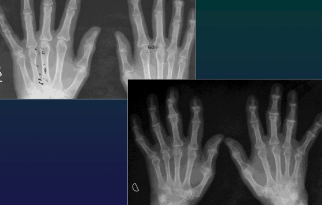

Hand

Polyarthrosis (DIPh, Trapezo MC1)

RA

CharaK RA hands

Focal soft tissue swelling

early=> MCPh, PIPh, ulnar styloid

OP

early=> juxtaarticular, band

late=> diffuse

Erosions

early=> decreased cortical differentiation (dot dash pattern)

marginal = moue ears at basis of the phalanges

subchondral=> pen in cup, destruction of ulna, carpal bones

Cartilage destruction

early false increased of joint space (effusion)

destruction & narrowing of joint space

Subchondral cysts

Malalignement

carpal: ulnar deviation and scaphoid luxation

fingers: MCPh, ulnar deviation, subluxation

RA hand joints

Dg CLUES

Purely erosive

Joint alignement changes

LOC

Classic: symétrie (+ unilateral in early stages)

Early: MCPh, distal RU, RC

Late: PIPh, IC

Almost NEVER involved DIPh